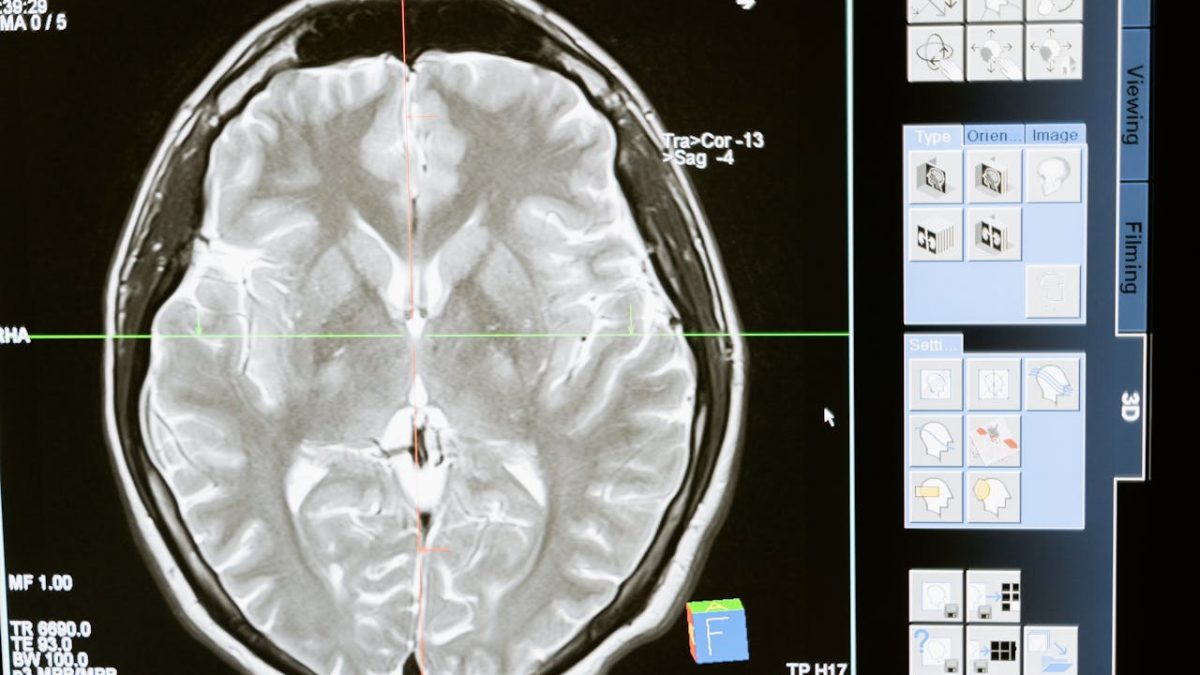

O estudo do impacto da obesidade na estrutura cerebral comparou os exames de 341 pessoas com Índice de Massa Corporal superior a 30, 341 pessoas diagnosticadas com Alzheimer e comparou estes dados com mapas de 682 participantes do estudo considerados saudáveis. Os resultados apontam para uma diminuição das zonas cerebrais que envolvem a aprendizagem, a memória e o julgamento.

“Mostrámos que há uma semelhança entre os cérebros de pessoas obesas e as que têm Alzheimer”, afirma principal autor do estudo, Filip Morys, investigador em neurociência e pós-doutorado na Universidade McGill, de Montreal, Canadá. Para o especialista, uma das respostas está na “espessura do córtex cerebral”, a camada externa do cérebro.

Se as análises prévias feitas pela ciência nos últimos anos indicavam risco de a obesidade incrementar a prevalência da doença de Alzheimer por via dos danos provocados nos vasos sanguíneos do cérebro e acumulação de proteínas, esta investigação (que pode consultar no original aqui) veio apontar semelhanças.

“O estudo mostrou que indivíduos obesos e aqueles que padecem de Alzheimer têm áreas comuns do cérebro que são menores em tamanho, possivelmente devido a um processo neurodegenerativo”, o que significa que as “células nervosas nessas regiões podem estar a sofrer danos e podem estar a morrer”, acrescenta a especialista em metabolismo Sabrina Diano, diretora do Instituto de Nutrição Humana do Columbia Irving Medical Center.